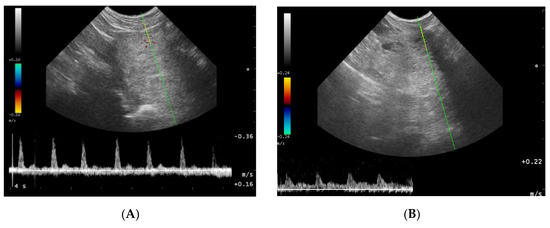

2.5. B-Mode Ultrasonography—Testes

3.3. Testicles B-Mode Appearance